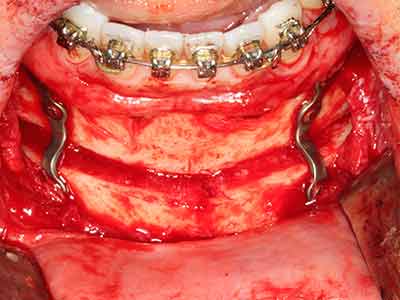

La piezochirurgia presenta altri vantaggi per quanto riguarda la raccolta di blocchi ossei. Oltre all'elevata precisione dell'osteotomia appena descritta, l'utilizzo di puntine per sega molto sottili permette di minimizzare in maniera significativa la perdita di materiale. È molto probabile che si verifichi una maggiore perdita di materiale durante la raccolta utilizzando puntine di strumenti più spessi, in particolare delle frese Lindemann (Lakshmiganthan, Gokulanathan et al. 2012). La separazione basale, necessaria in particolare per i trapianti di blocchi nella zona retromolare, viene semplificata grazie a seghe specificatamente progettate di forma rettangolare; di conseguenza la piezochirurgia è considerata una procedura precisa, semplice e sicura per la raccolta di blocchi di osso nella zona retromolare (Happe 2007) (figg. 1-12).

Il tessuto osseo non è semplicemente una struttura minerale, ma contiene anche una percentuale significativa di fibre di collagene. Ciò significa che non possiede solo una buona forza di compressione, ma anche un certo livello di flessibilità che è possibile sfruttare durante l'esecuzione degli accrescimenti di osso. Nella procedura di espansione classica con incisione ossea, la cresta alveolare atrofizzata viene incisa longitudinalmente ed espansa con cautela dopo aver raggiunto una profondità di osteotomia adeguata (figg. 13-16), idealmente senza una sostanziale rimozione del periostio (Brugnami, Caiazzo et al. 2014, Stricker, Fleiner et al. 2014). I sistemi a piastra e vite con distanza di espansione incrementale si sono dimostrati efficaci nella separazione delle due lamelle ossee restando al di sotto della soglia di frattura. In generale, sono richieste larghezze dell'osso residuo di almeno 3-4 mm (Chiapasco, Zaniboni et al. 2006) per garantire un'adeguata flessibilità e una copertura sufficiente dell'osso per gli impianti futuri. Se necessario, un'osteotomia di rilascio verticale su uno o più lati può migliorare la flessibilità. Una combinazione con ulteriori tecniche di accrescimento, in particolare dal lato buccale, è stata descritta come un'alternativa alla tecnica classica.

La procedura di incisione è particolarmente atraumatica e non comporta una perdita significativa di dimensione durante l'utilizzo delle seghe piezoelettriche, così come non si notano differenze rilevanti tra impianti in mandibole incise e impianti in una cresta alveolare senza deficit osseo (Chiapasco, Zaniboni et al. 2006, Danza, Guidi et al. 2009). Una sufficiente irrigazione continua è essenziale, tuttavia, in particolare con incisione profonda e localmente ristretta, per prevenire la sollecitazione termica nelle regioni apicali dell'osteotomia.